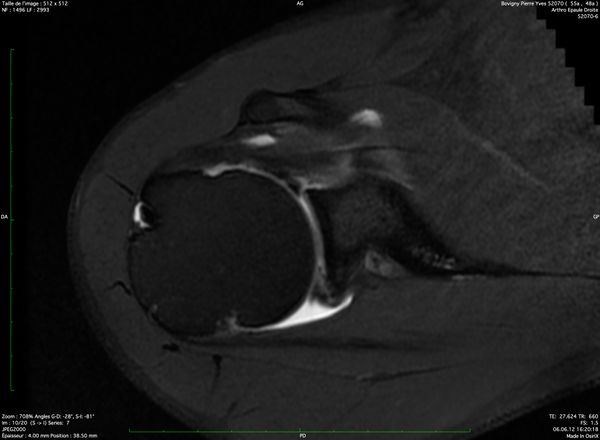

Computed tomography (CT) and magnetic resonance arthrography (MRA)

Examinations using intra-articular injection of a contrast medium (CT and MRA) are more reliable than simple MRI to visualize labral lesions and articular rotator cuff lesions (Figures).

MRA finding

Magnetic resonance arthrography (MRA) finding

Magnetic resonance arthrography (MRA) is standard, because it can also reveal the possible presence of a paraglenoid cyst (Figure) communicating with a labral tear, while allowing analysis of any concomitant tears (rotator cuff, osteochondral), and eliminate other causes of pain (acromioclavicular arthropathy, subacromial bursitis, tears relating to a painful and unstable shoulder).

Reliability depends on both machine and operator efficacy, but Jung et al. report a sensitivity of 85% and a specificity of 86% for superior labral tears.[41]

ABER position further improve sensitivity.[42]